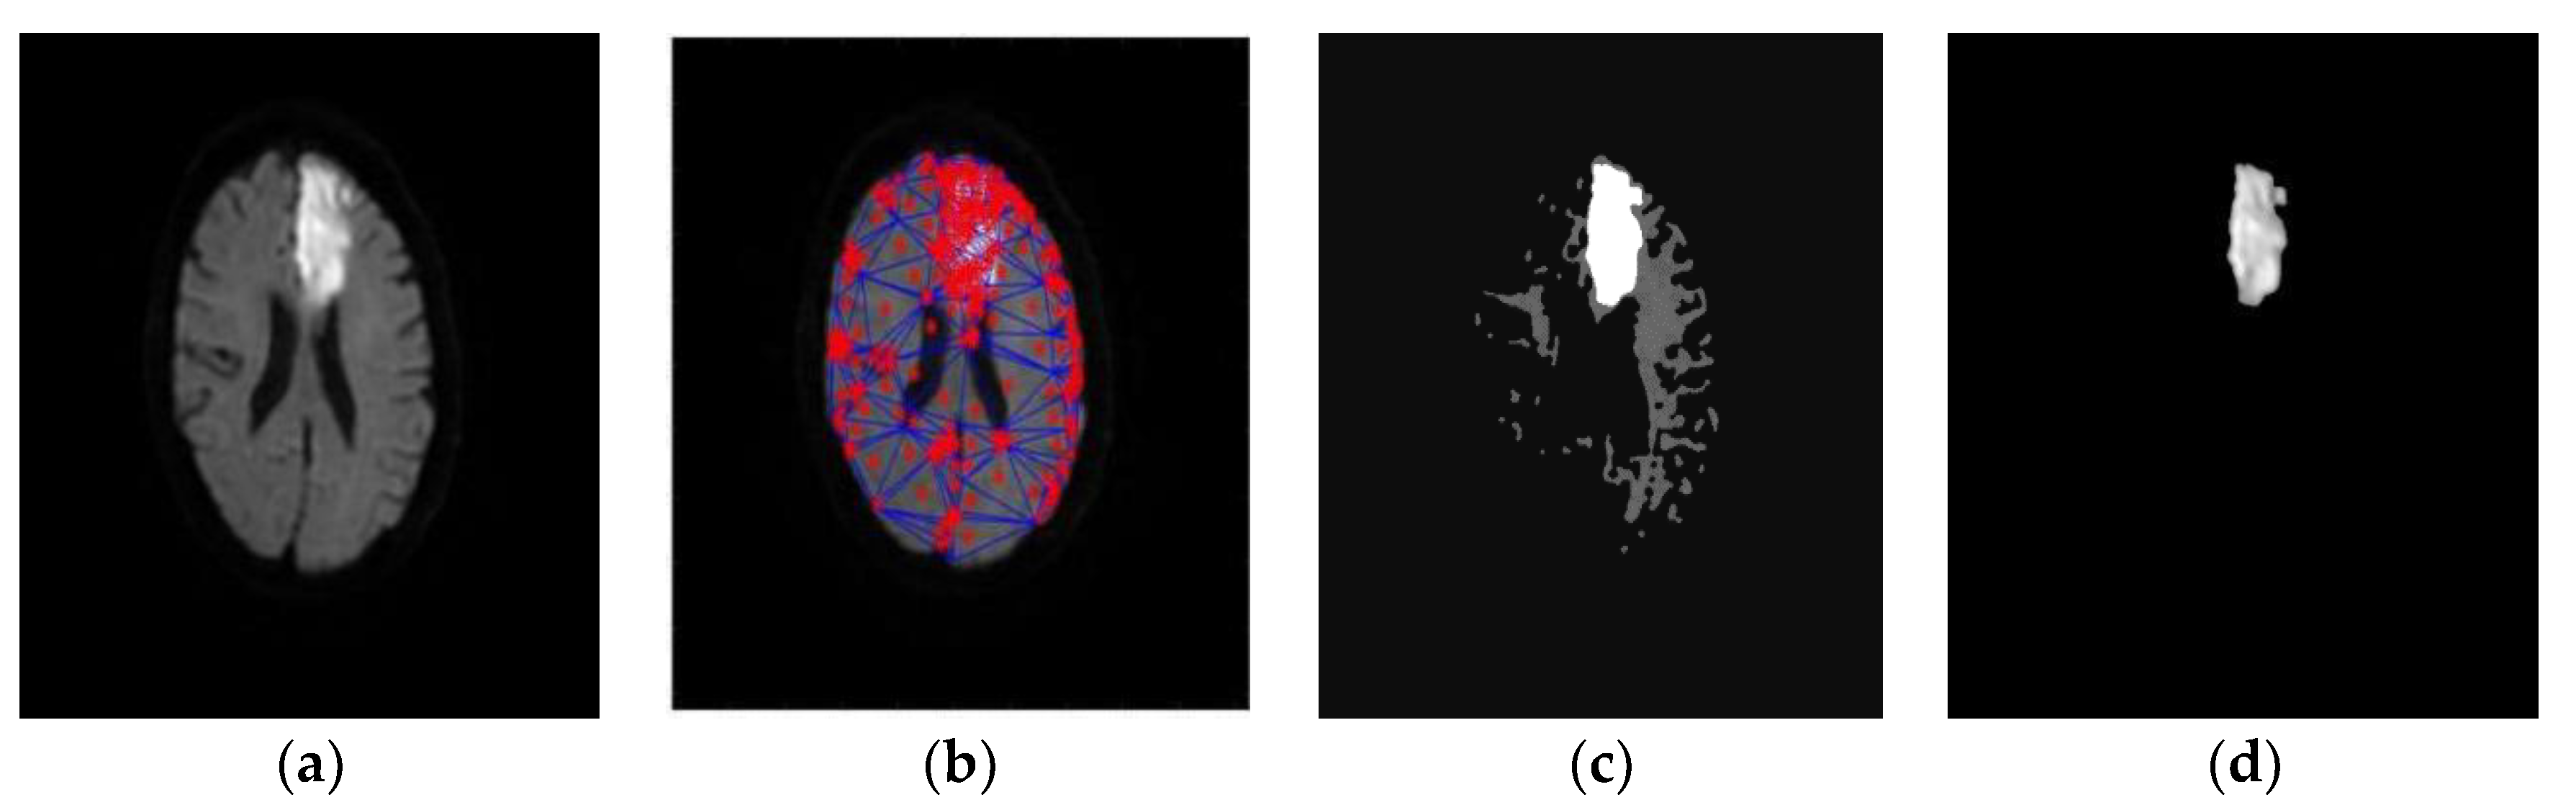

- Subudhi, A.; Acharya, U.R.; Dash, M.; Jena, S.; Sabut, S. Automated approach for detection of ischemic stroke using Delaunay Triangulation in brain MRI images. Comput. Biol. Med. 2018, 103, 116–129. [Google Scholar] [CrossRef]